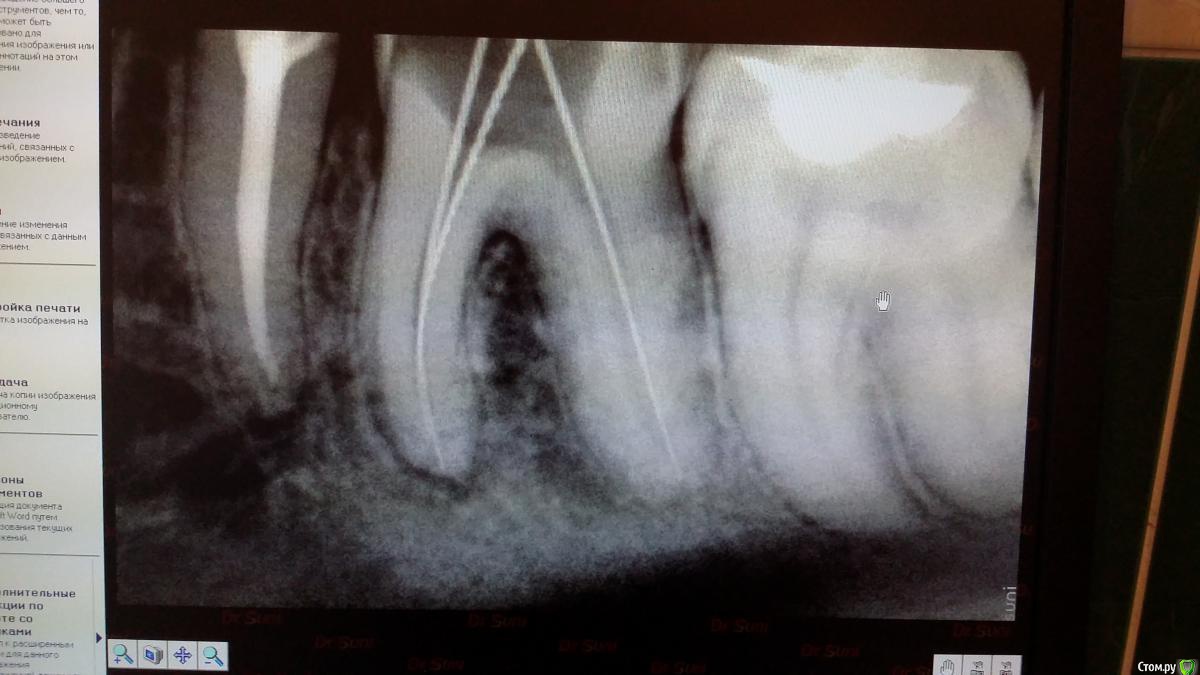

Recive Опубликовано 9 февраля, 2015 Поделиться Опубликовано 9 февраля, 2015 Жалобы: классический пульпит./периодонтитанамнез:эндэндодонтия первичнаялечение:ммо кк первое посещение пульперил, да не будет больеть! Аминь)Второе- в мщ, мя каласепт в дистальном метапаста (ннагнитал каналонаполнителем в надежде найти дельту в апексе)Третье - через неделю замена каласепта на каласепт, и в дистальный крезофен, для надежности.Четвертое на 16.02 пломбировать если не будеет болеть. Ваше мнение и варианты .первый снимок при поступлениивторой при прохождениивторой контроль метапасты и каласепта1.02. 09.02. 1 1 Ссылка на комментарий

Чертков Александр Опубликовано 11 февраля, 2015 Поделиться Опубликовано 11 февраля, 2015 Оценивая динамику рентгенограмм посмею предположить что Вы там создали пробку из опилок - поскольку на рентгенограмме с инструментом Вы у апекса, а на следующей уже "недолёт"...отмывайте нормально канал (нет УЗ- активируйте инструментом) и пакуйте. Коронка - обязательно! 1 Ссылка на комментарий

Recive Опубликовано 11 февраля, 2015 Автор Поделиться Опубликовано 11 февраля, 2015 Оценивая динамику рентгенограмм посмею предположить что Вы там создали пробку из опилок - поскольку на рентгенограмме с инструментом Вы у апекса, а на следующей уже "недолёт"...отмывайте нормально канал (нет УЗ- активируйте инструментом) и пакуйте. Коронка - обязательно! Хм....мыл на 2м посещении очень много(минут 5 один канал), дабы отмыть метапасту.там 08 ример стучит как в пробку... Ссылка на комментарий